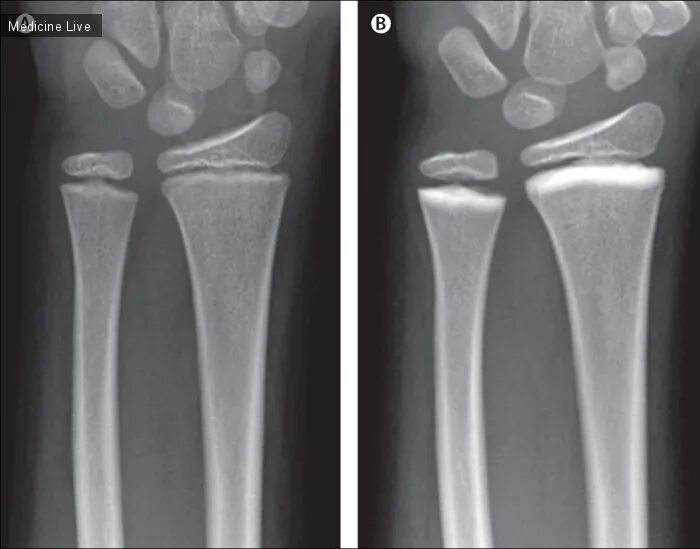

Остеосклероз костной ткани